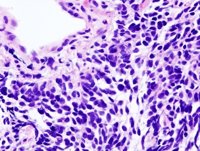

Los niveles de glóbulos blancos pueden predecir si los pacientes con cáncer de pulmón responderán a la inmunoterapia

Glóbulos Blancos

BOBJGALINDO/WIKIMEDIA COMMONS